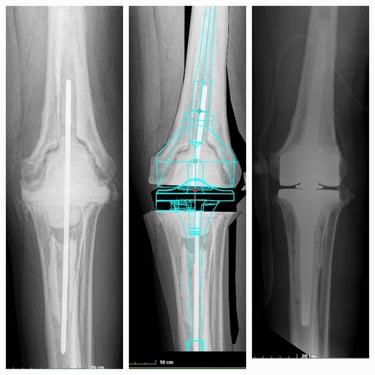

Artroplastia de rodilla (prótesis total/parcial).

Cirugía de revisión de cadera y rodilla.

Cirugía robótica de cadera y rodilla (en casos seleccionados).